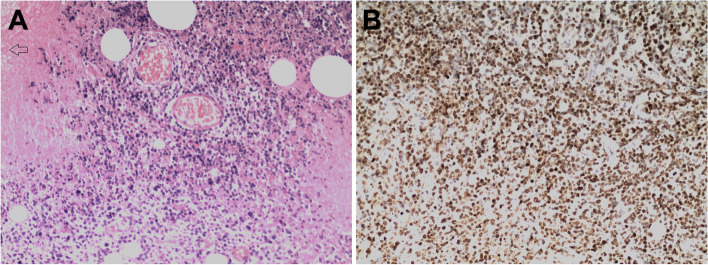

Methods: The clinical and histological characteristics of 42 ENKTCL cases were retrospectively evaluated. Del-LMP1 was detected using a nested polymerase chain reaction and Sanger sequencing, while LMP1 protein expression was assessed via immunohistochemistry. Overall survival (OS) was analyzed.

Results: The LMP1 gene was identified in 37/42 ENKTCL cases, including 2 wild-type (wt-LMP1), 35 del-LMP1 cases. LMP1 protein expression was positive in 21/42 cases. In the control group, the LMP1 gene was detected in 6/10 cases, all of which were del-LMP1, and the LMP1 protein was positive in 4/10 cases. Fisher's exact test revealed no significant differences between the two groups in the LMP1 gene, del-LMP1, or LMP1 protein expression. Additionally, there was no significant correlation between del-LMP1 and LMP1 protein expression and clinical characteristics such as age, gender, or vascular invasion. However, LMP1 protein expression was significantly higher in necrotic tissues (p = 0.030) and younger patients with del-LMP1 (p = 0.004). Survival analysis showed no significant difference in OS between wt-LMP1 and del-LMP1 patients (p = 0.331) or between LMP1-positive and -negative cases (p = 0.592).